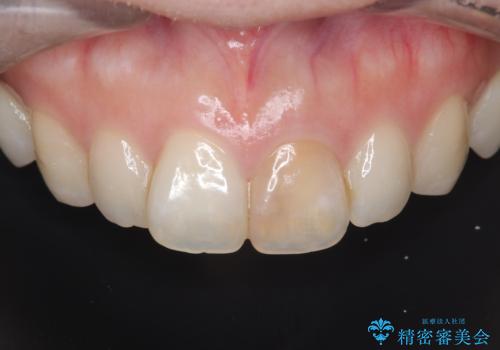

治療では、変色した歯を形成した後、精密なシリコン印象材で型取りを行いました。この型取りから、患者様の歯の色や形、透明感を忠実に再現したオーダーメイドのオールセラミッククラウンを作製。金属を一切使わないため、アレルギーの心配がなく、歯ぐきの変色も防ぎます。技工士と連携し、天然歯と見分けがつかないほどの自然な仕上がりを追求。機能性と審美性を兼ね備えた、理想的な前歯を取り戻していただけました。